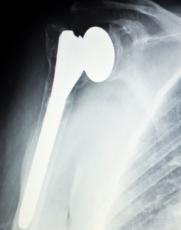

What is Total Joint Replacement? Total joint replacement, or TJR, is an orthopedic surgical procedure typically performed in a hospital or outpatient surgery center. During the procedure, a patient’s damaged cartilage and...